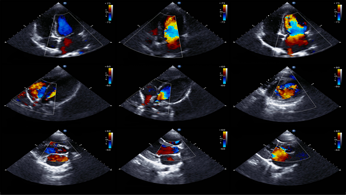

L’ecocardiogramma è una tecnica che si basa sull’impiego di ultrasuoni e consente di vedere dall’interno sia le pareti del cuore sia le sue strutture interne (come le valvole) e di valutare esattamente la contrattilità del cuore globale.